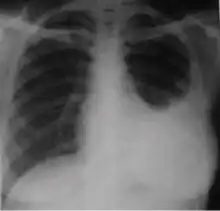

-

Chest x-ray showing bilateral hilar adenopathy of primary pulmonary TB